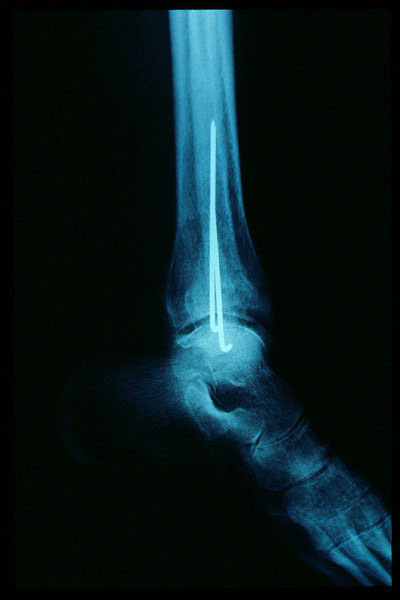

Fractura maleolo externo. Osteosíntesis.